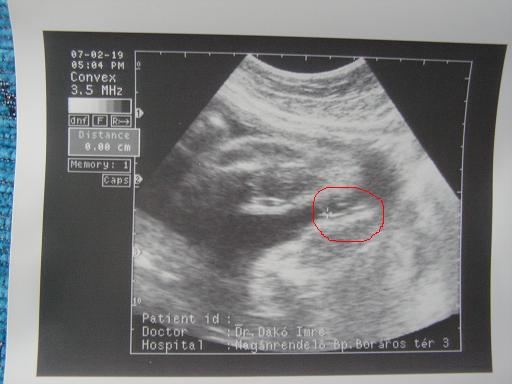

Ja, nekem is van uh-hírem. (Képem nincs, még a nemét sem nézték.

) Egy jó és egy rossz hír (megint). A jó: felszívódtak a ciszták a baba fejében. (Egy hét alatt!) A rossz: meszes a lepény. Utánanézek majd, mi mindent jelent ez. Az u-os nagyon csóválta a fejét, de a genetikus orvos, akivel utána beszéltünk az eredményekről, nem tulajdonított nagy jelentőséget ennek. Azt mondta, akkor lenne baj, ha a baba nem fejlődne jól. Ehhez képest 2 héttel nagyobbnak tűnt a koránál.

És meghaladta az 1 kilót! MAjd elmondom azt is, mit mondott a dokim (délelőtt hívom).